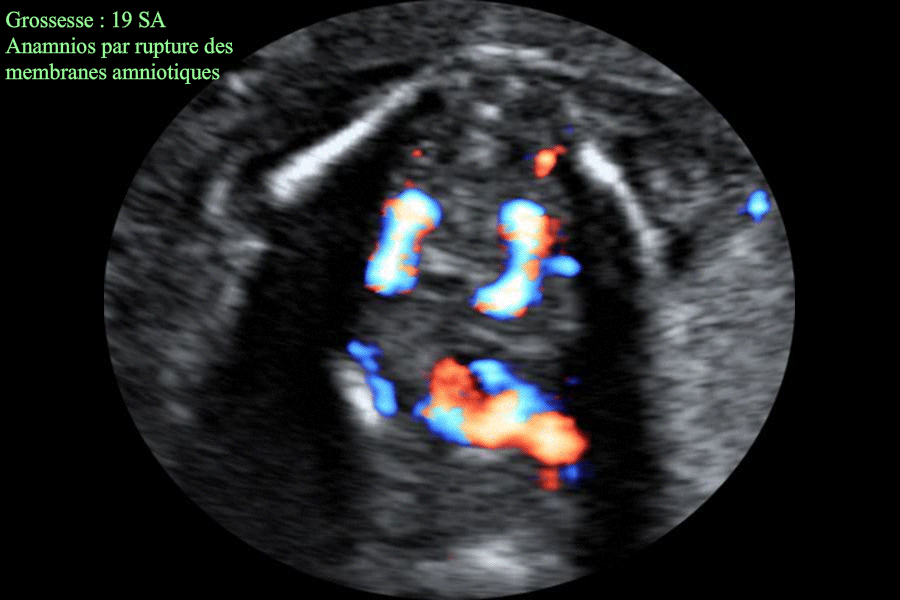

Anamnios par rupture prématurée des memebranes à 19 SA - Individualisation de la vessie

Images échographiques montrant un anamnios à 19 SA ; conséquence d'une rupture prématurée des membranes survenant 36 heures auparavant.

L'image échographique montre l'absence totale de liquide amniotique avec la mise en évidence de d'une vessie qui se remplit et se vide régulièrement ; cela permet d'éliminer la présence d'une pathologie de l'arbre urinaire pouvant donner échographiquement les mêmes images.

Les autres images échographiques montrent également, dans le présent cas : le repli du rachis fœtal ; le repli du placenta et deux reins normaux.